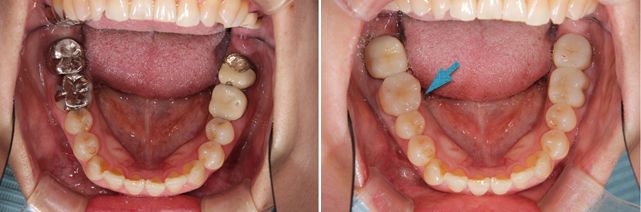

術前術後です。矢印の部分がオールセラミックインレーです。

セラミックインレー

費用11万円

リスクとして歯を削る量が多いため痛みが出る可能性と強い力によって割れる可能性がある。